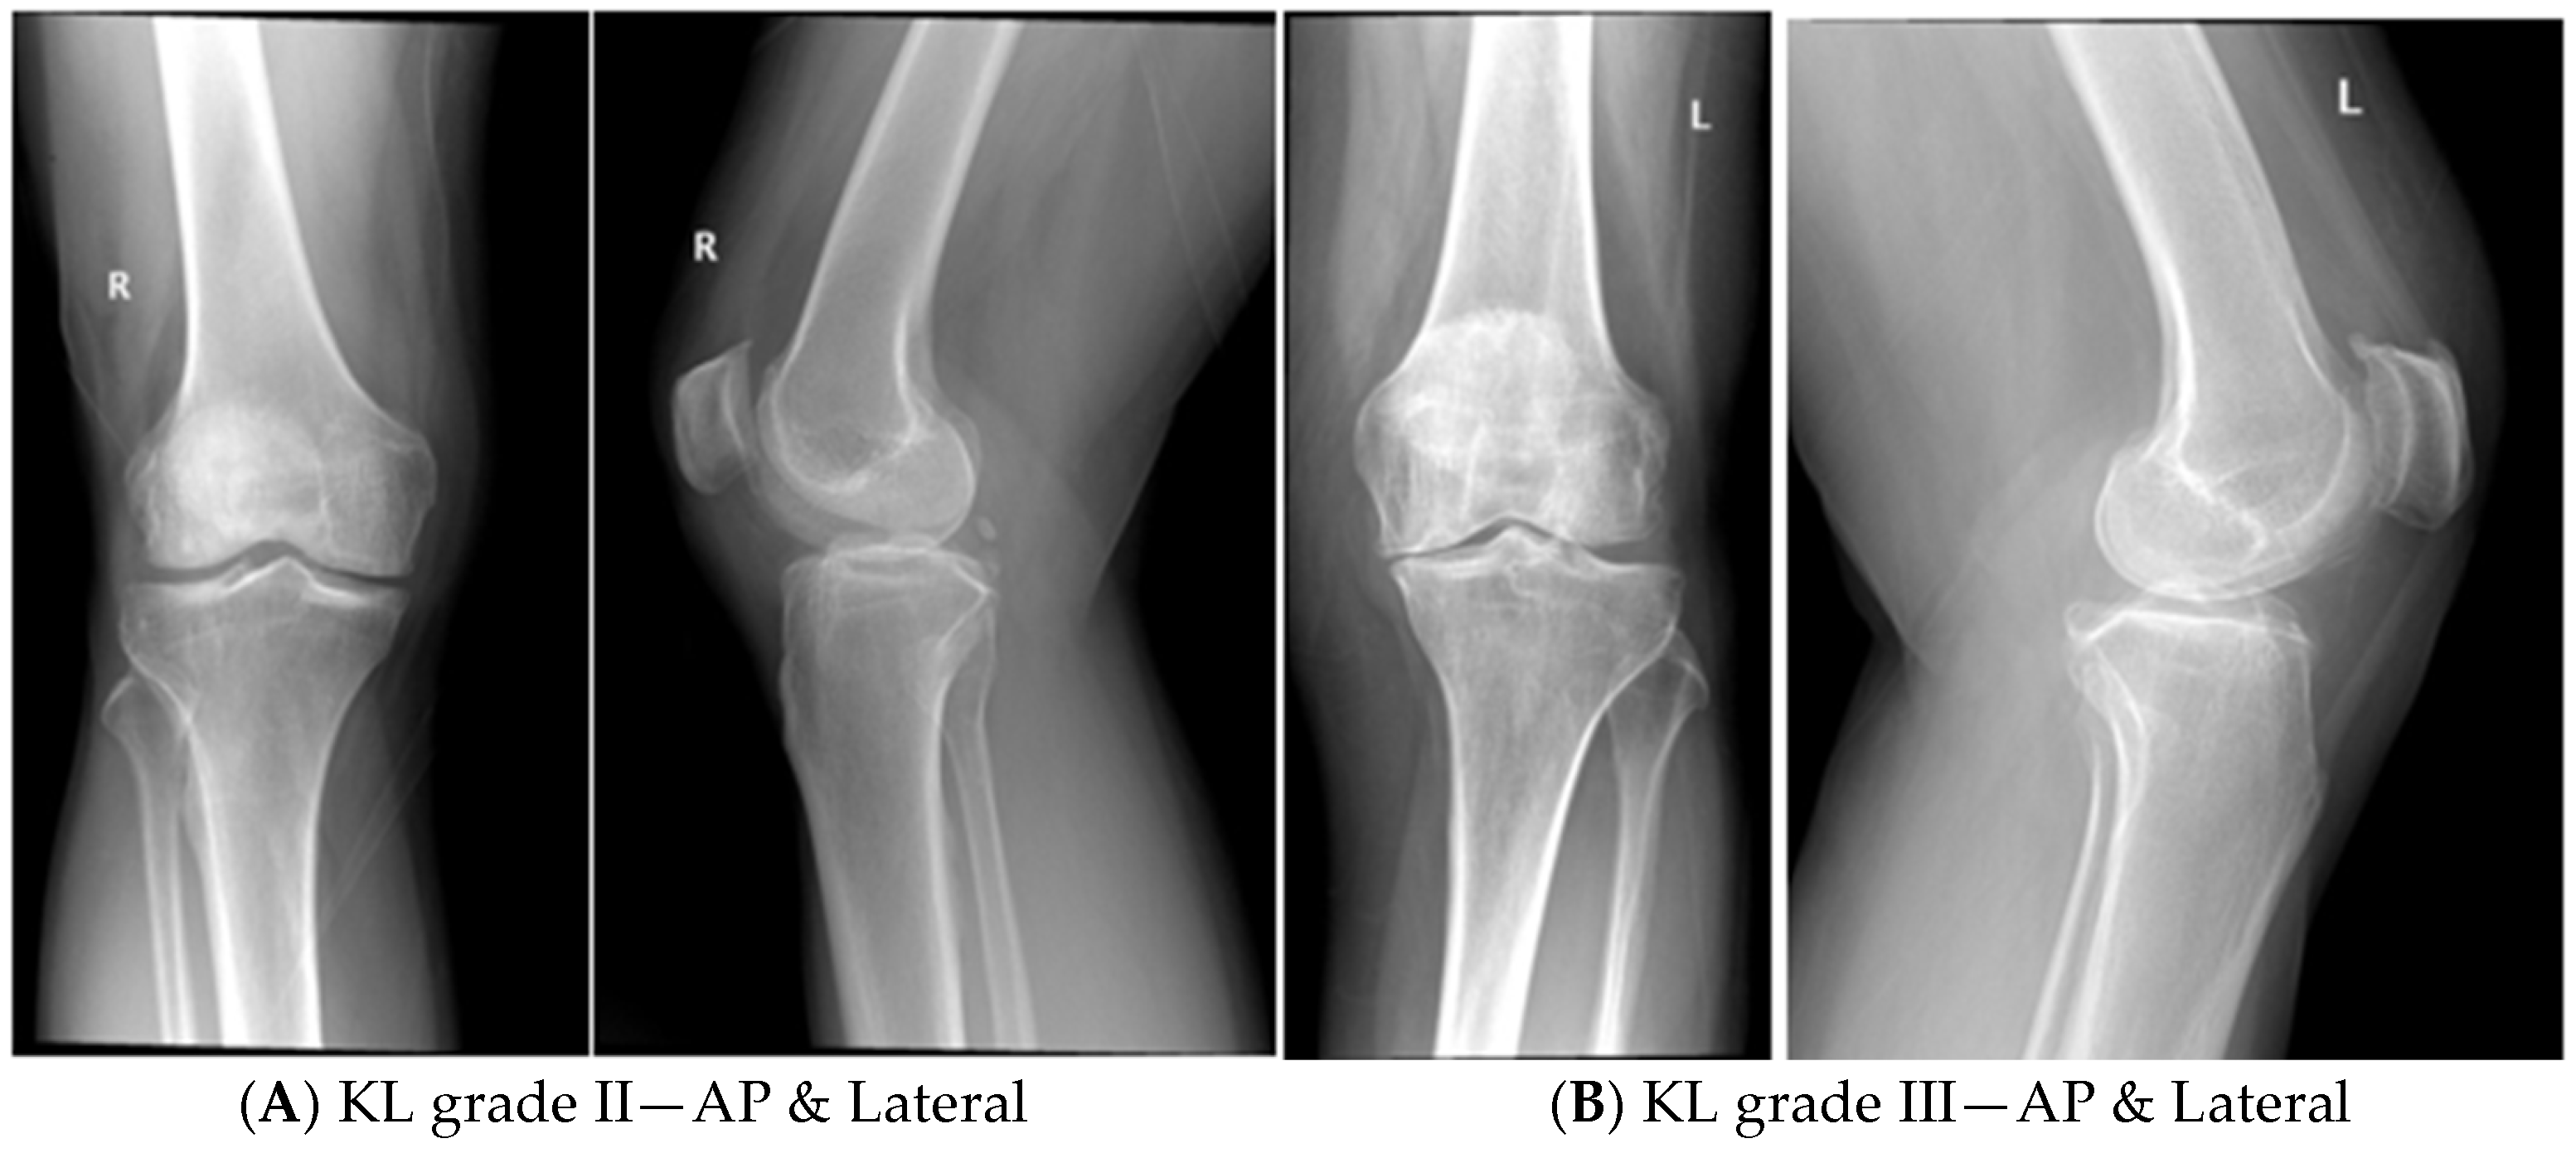

- Patients of KOA with radiological grading of KL grade II and III.

- KOA patients with KL grade IV were excluded, as it has global cartilage loss with subchondral erosions and deformities.